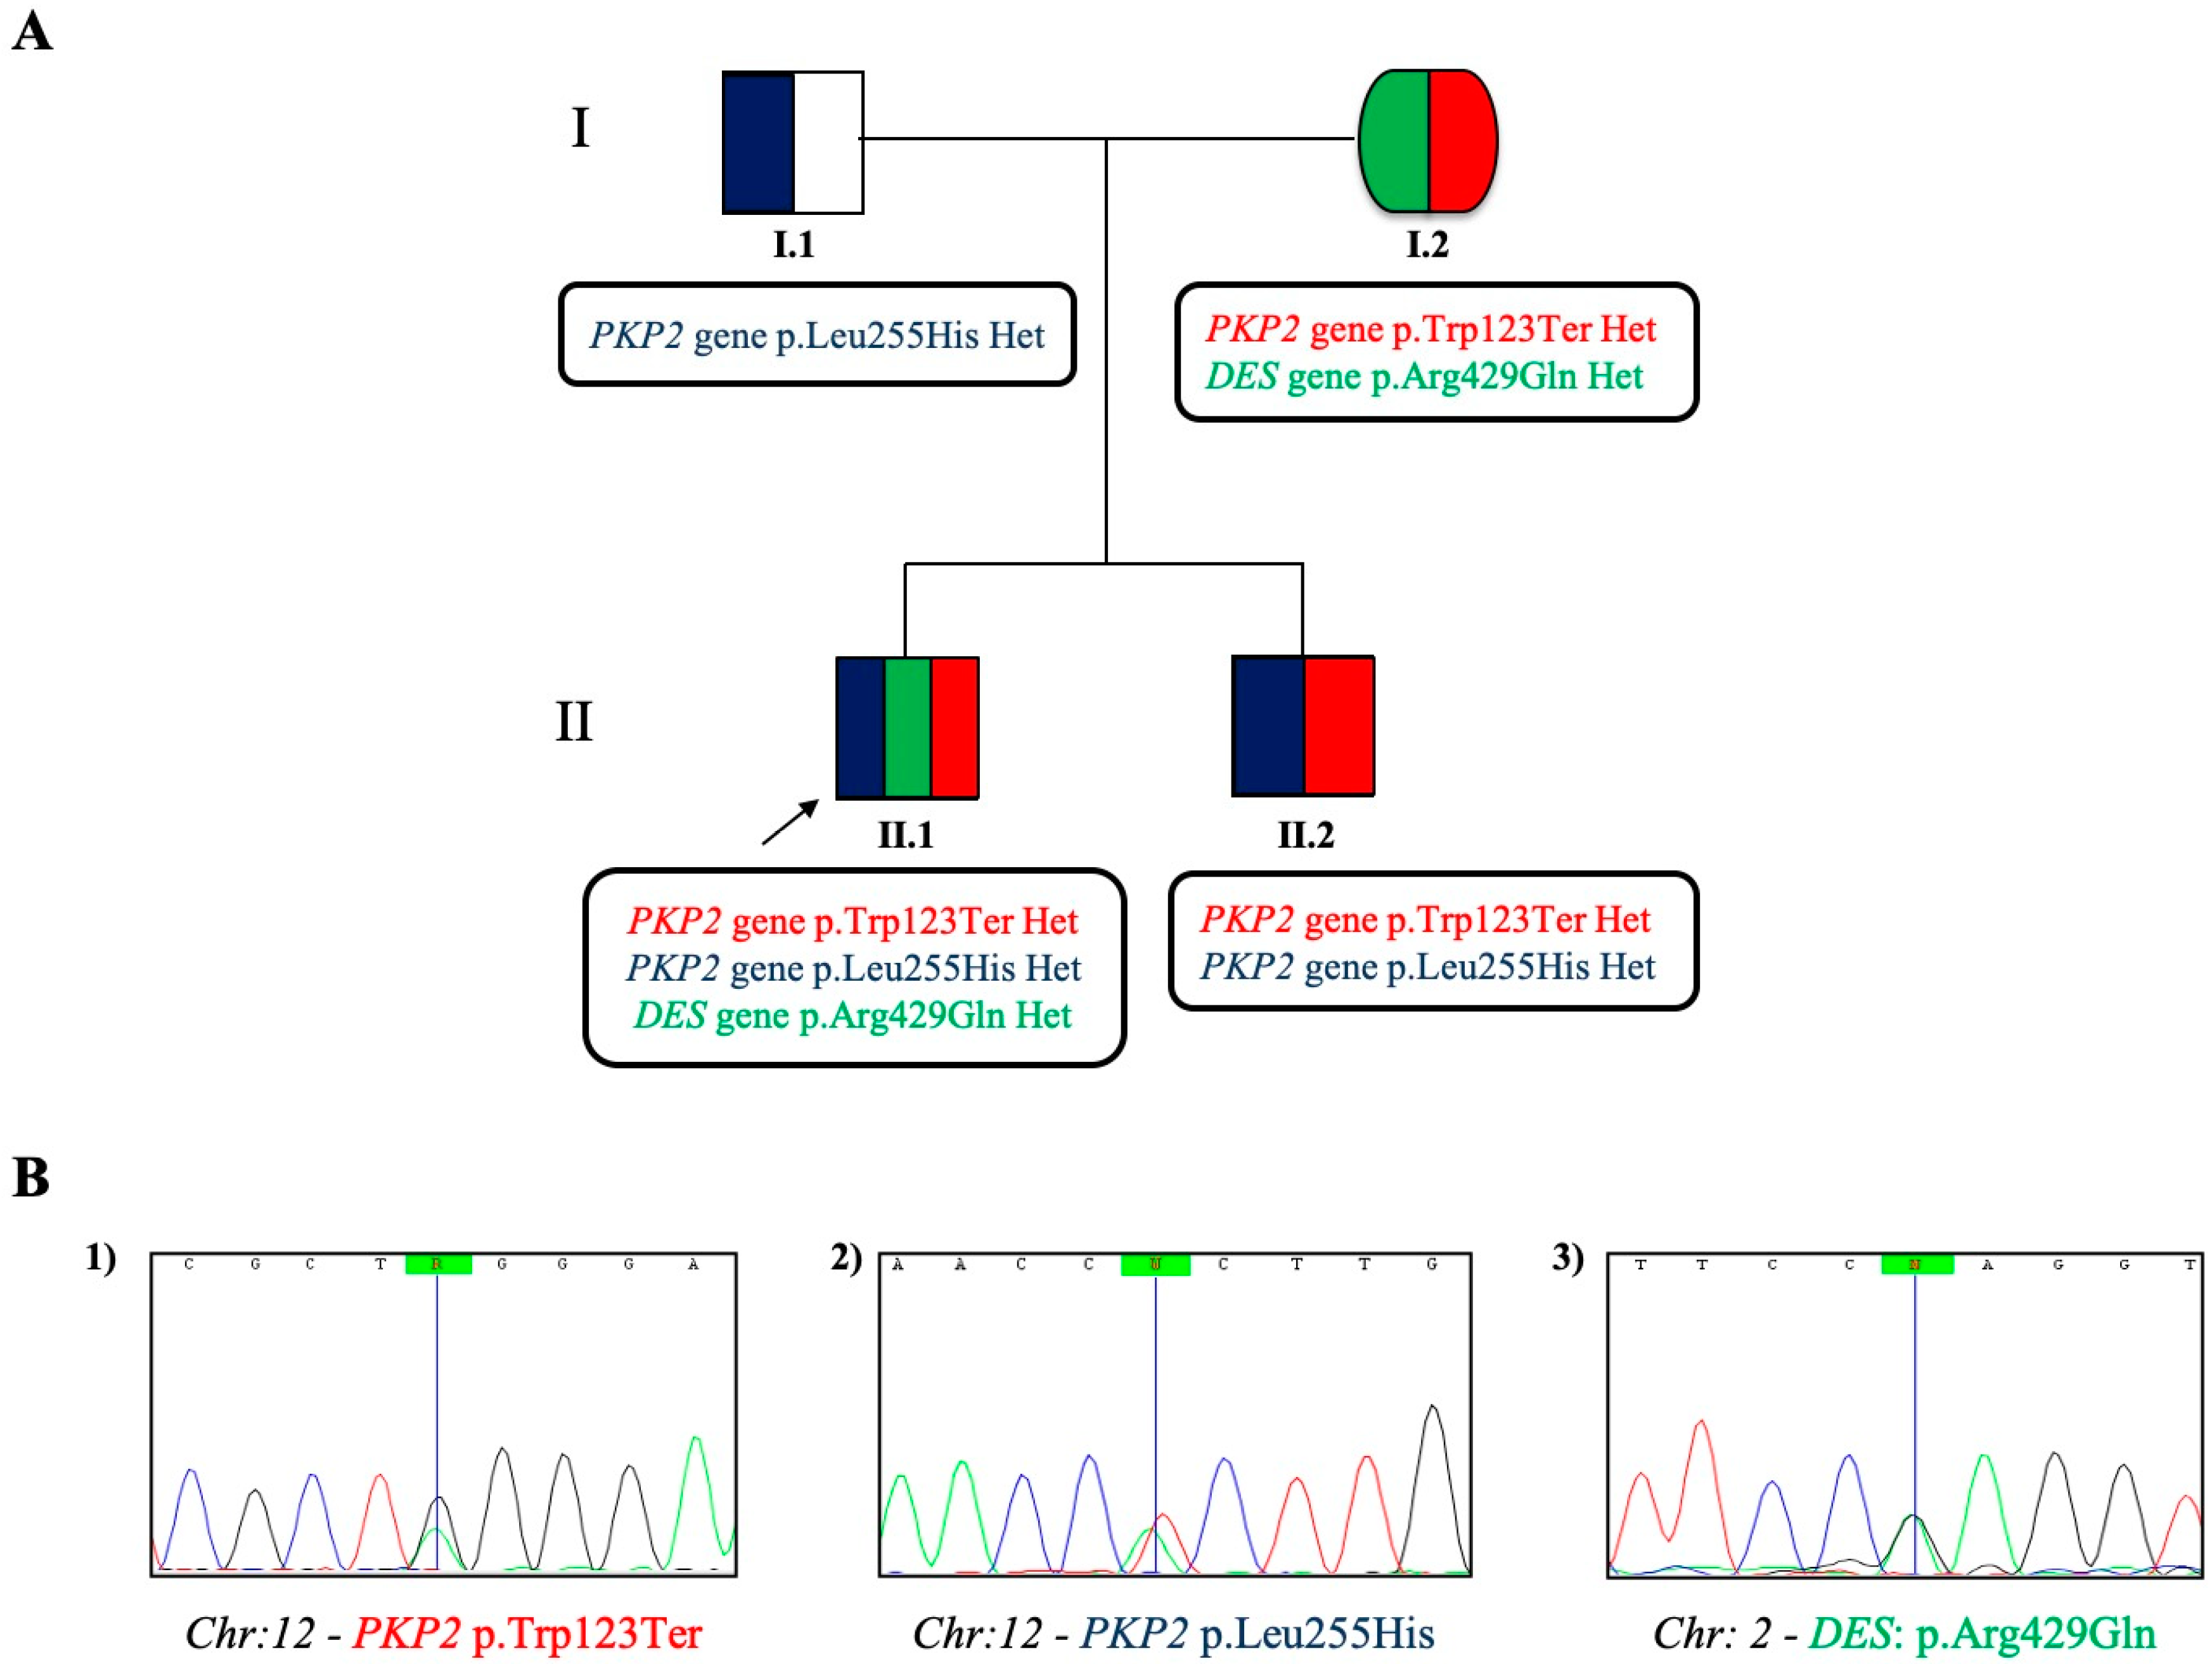

2.1. Case Study Presentation and Clinical Description

2.2. Case Study: Clinical Molecular Biology Investigation